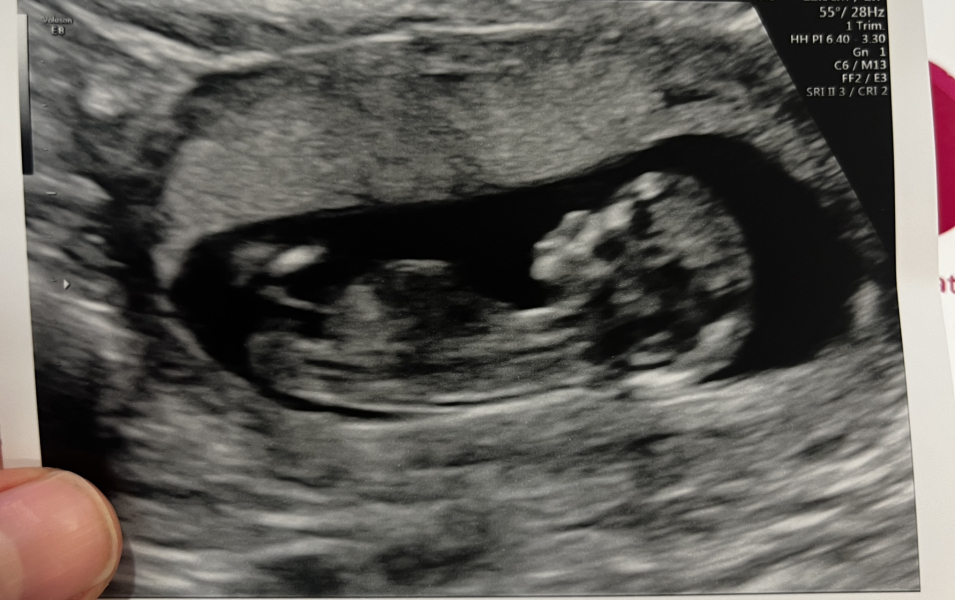

@MrsJGrealish hahaha yes sorry talking about dogs now 🤣 lol some pictures I'm like is there even one there 😂 tbf I thought this was one of the clearest scan pics I've had I looked back on DS and there was no nub in sight it was a terrible picture

Loving the scan pics @bringmearainbow!

@bringmearainbow amazing!! That scan pic is so clear!! You know my scan pic was super clear too and I could already see on the scan as the nub was sooo obvious. And it was super obvious on my photo. A during my scan at 13 weeks I thought that’s a girl nub. It’s a girl. An I was right. I just knew it.

If what I can see is yours is a nub. Which I think it is… that a girl. I’m certain of it 💗 time shall tell. How exciting!!